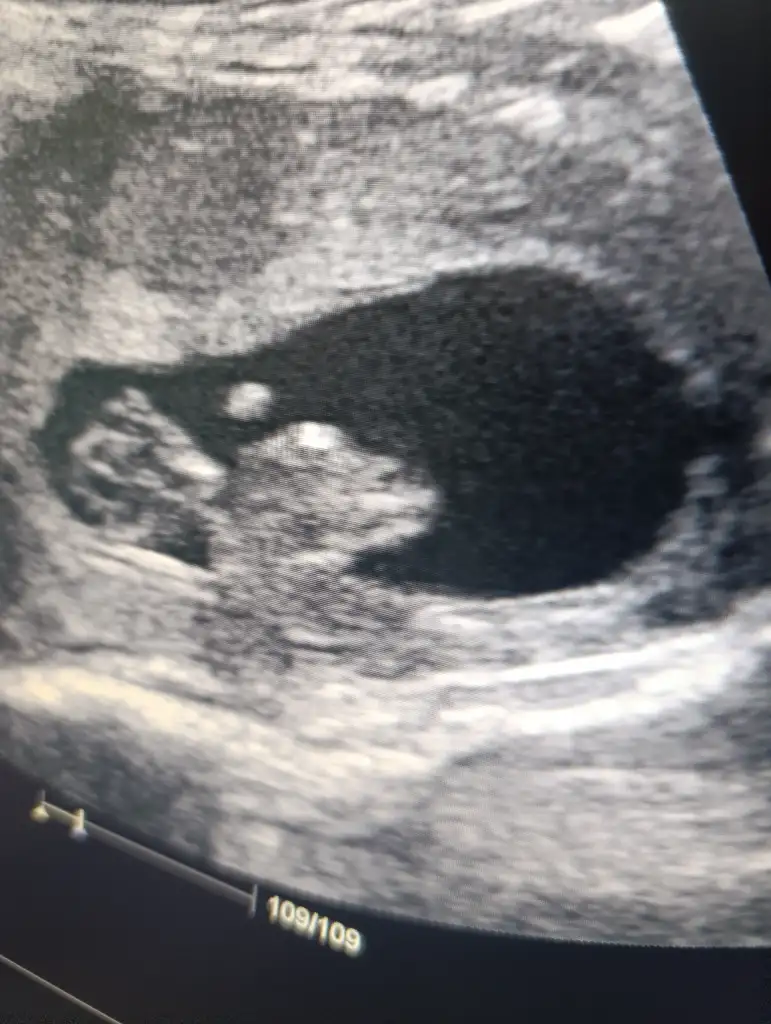

çok küçük ama kese kız gibiBana da yorum yapar mısınız 8 haftalık vajinal bakıldı

Ayy insallah ağzınız bal yesinçok küçük ama kese kız gibi